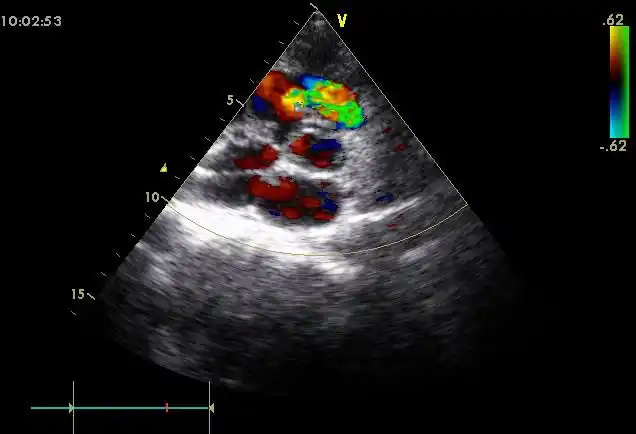

西安市第三医院心脏超声是什么

心脏超声标准切面及测量

心脏疾病的超声诊断技巧ppt

纯干货心脏超声经验分享

孔令秋哪些心脏超声表现几乎没有临床意义

绝对完美的胎儿超声心脏切面

心脏.超声